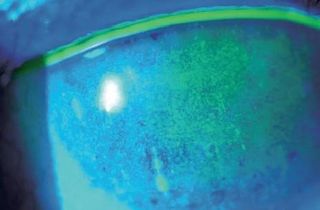

Le frottement des cils

(aussi appelé trichiasis) sur le globe oculaire provoque une gêne importante et peut avoir des conséquences grave sur la cornée. Au delà de l'inconfort qu'il procure, lorsque ce frottement n'est pas pris en charge il peut provoquer une kératite, voire un ulcère de la cornée

ou dans les cas extrêmes, une perforation de la cornée.